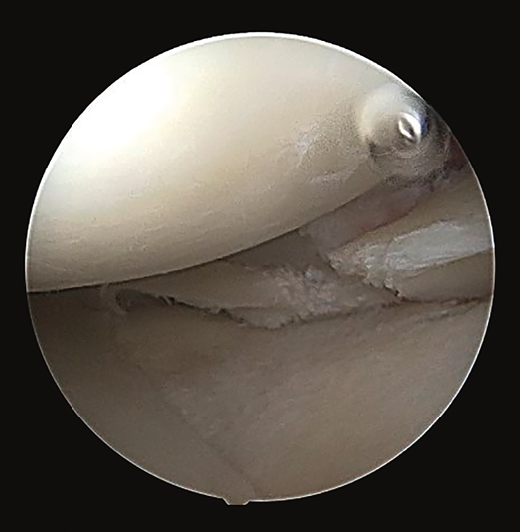

Las radiografías simples mostraron avulsiones óseas en la parte posterior de la tibia (Figura 1).

Figura 1. Radiografía de perfil de la rodilla donde se observa la afectación ósea en la parte posterior de la tibia.